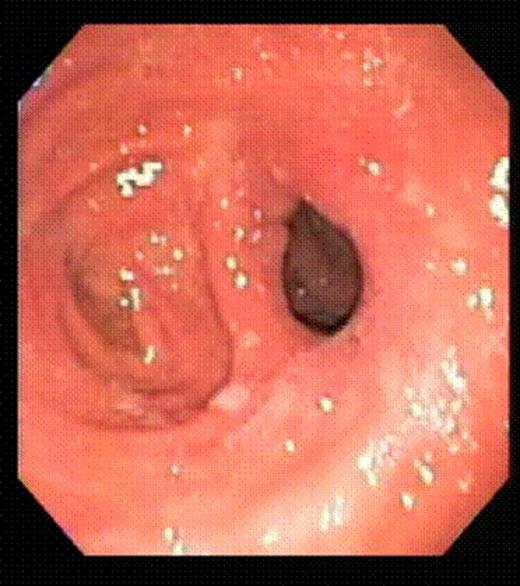

This 47-year-old man underwent a RYGB with a 30cc pouch, a 12mm circular stapled GJ and a 150cm long Roux limb in 2005. He lost 75kg with a reduction of BMI of 23.3 (63.7 to 40.4), achieving his lowest weight 3.25 years after his RYGB. The patient started experiencing dumping syndrome and regained 7kg in weight over the next 11 months, going up to a BMI of 42.5. An upper GI series x-ray showed an enlarged gastric pouch. An oesophago-gastro-duodenoscopy (OGD) showed a dilated GJ with loss of restriction. As an alternative to an open or laparoscopic revision, the patient elected to undergo endoluminal surgery using the StomaphyX™ device. The procedure was carried out under general anesthesia. An upper endoscopy was first performed to identify the anatomical landmarks of the pouch. The pouch length was noted to be 7 cm. The GJ was again observed to be widely dilated. The endoscope was then inserted through the shaft of the StomaphyX™ device, and the device and endoscope were introduced in tandem transorally into the pouch under continuous visualization. Once inside the pouch, vacuum was employed to draw large folds of gastric pouch wall tissue into the lumen of the device. With the gastric pouch wall on suction, the pouch wall was circumferentially plicated with serial firings of 6mm 3-0 polypropylene fasteners. This plication was in performed at two levels, one at 1 cm above the GJ anastomosis and one at 1 cm below the gastro-oesophageal junction. In total, 22 fasteners were delivered. A completion endoscopy was performed after the plication which showed that the 7-cm pouch had been reduced to 3 cm in length. The luminal diameter as well as the width of the GJ anastomosis was also significantly narrowed. The procedure took 40 minutes to perform with minimal intra-operative bleeding. There were no perioperative or postoperative complications.

Gastrojejunal stoma immediately after endoluminal gastric pouch plication